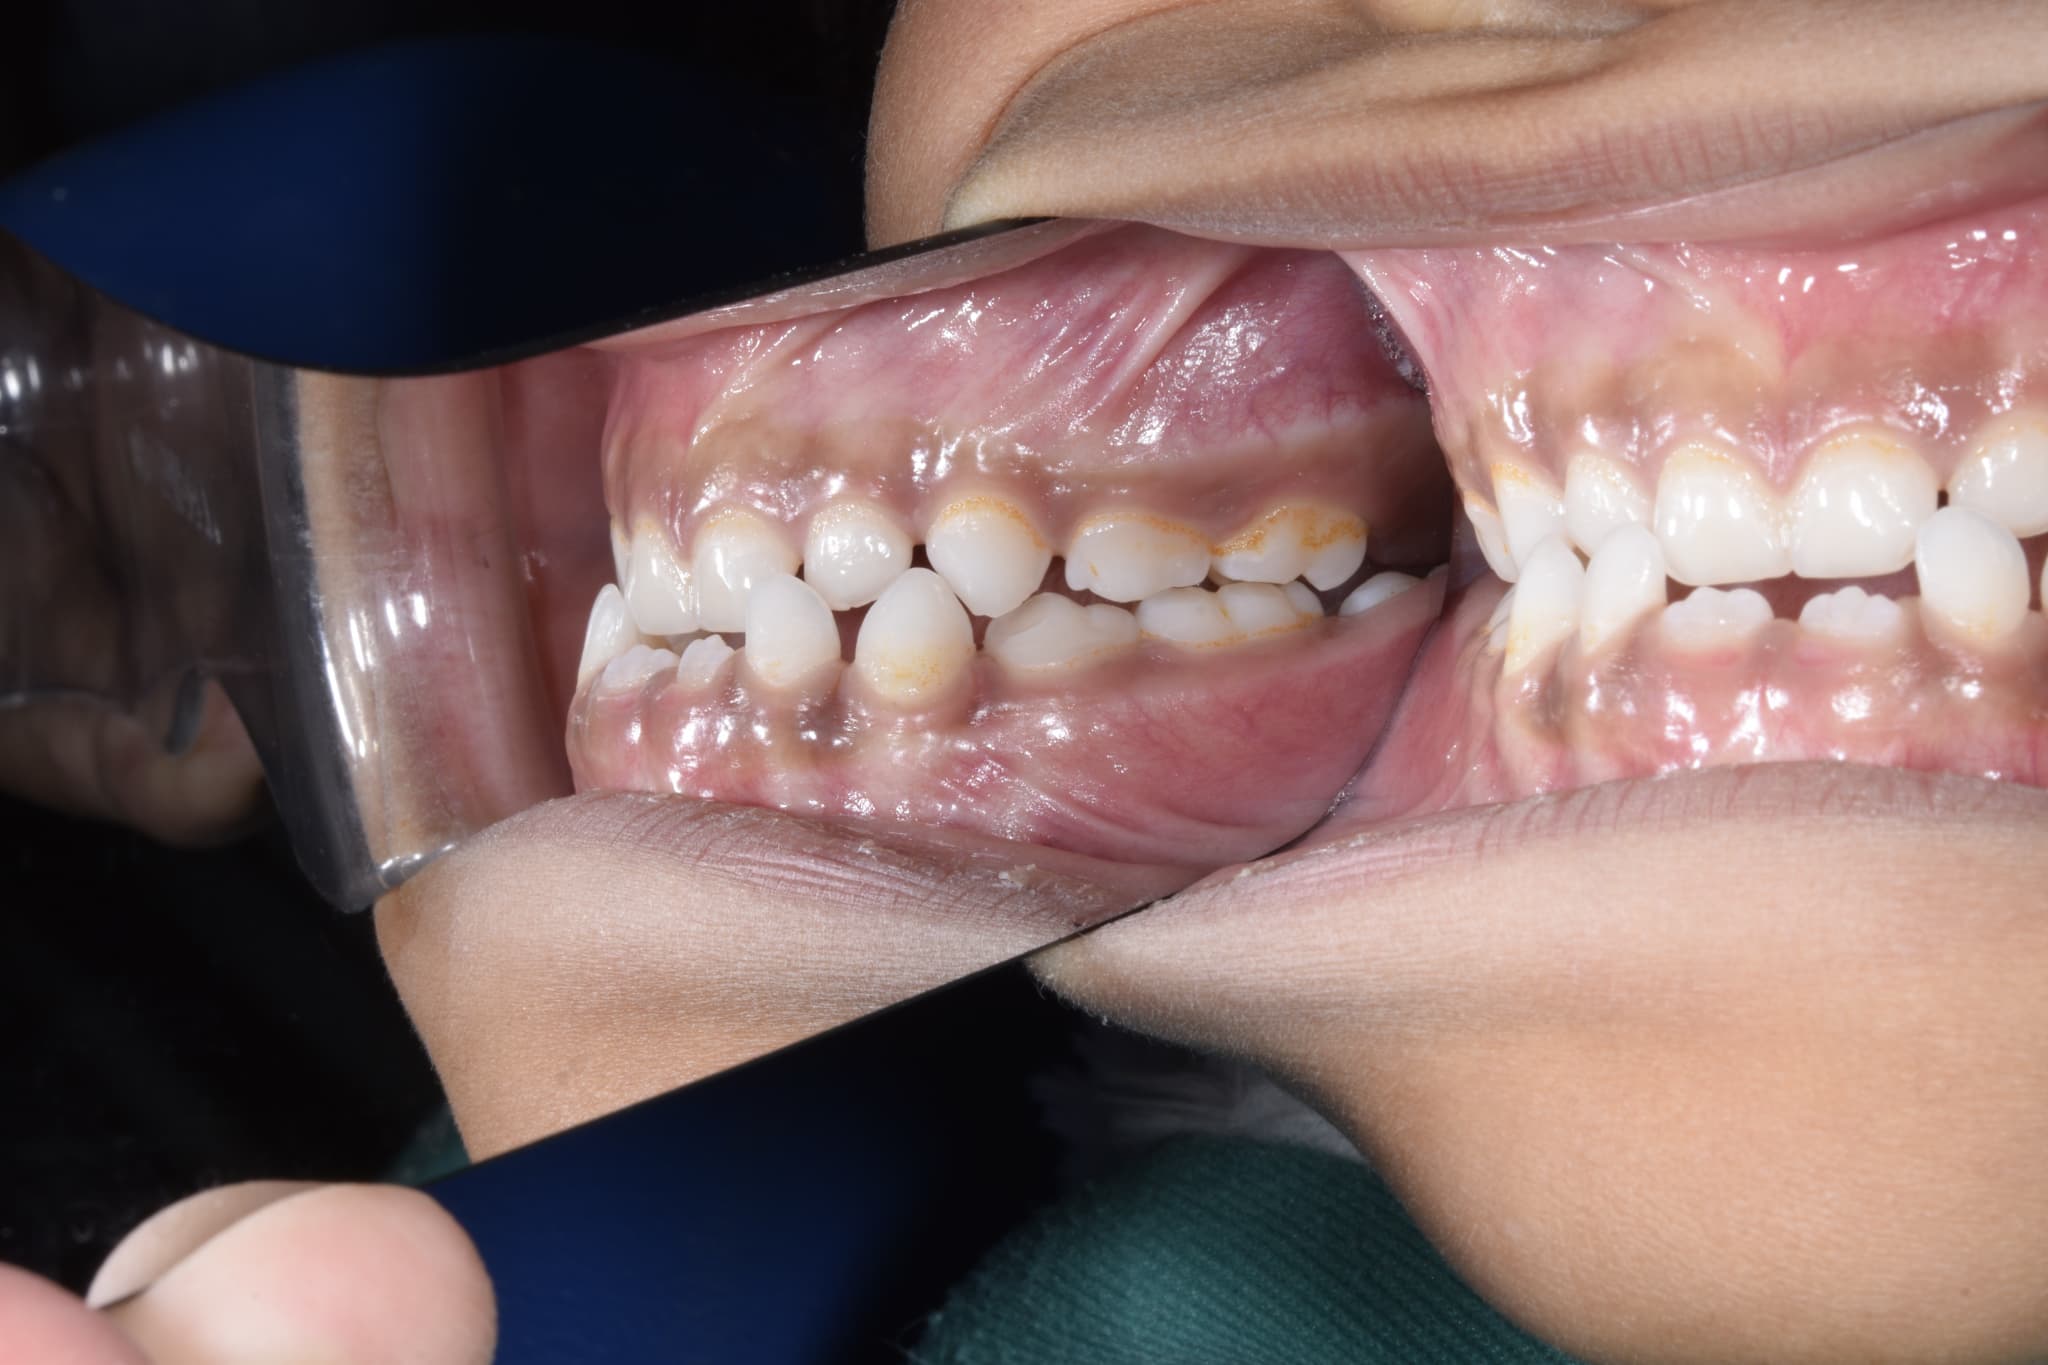

叢生(そうせい)は、歯がデコボコに生えていたり、重なり合っていたりする状態のことです。顎が小さくて歯が並ぶスペースが足りない場合に起こりやすいです。歯と歯が重なっていると歯磨きもしにくいため、虫歯や歯肉炎になるリスクが高くなります。